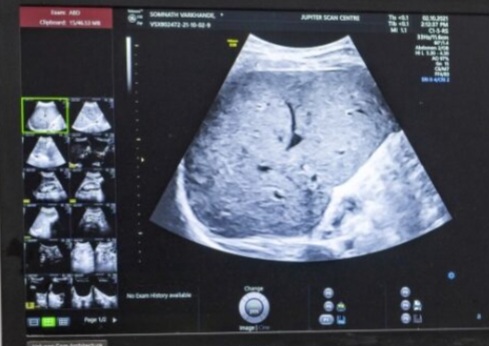

सिवनी मालवा / नगर के समीपस्थ बानापुरा में इन दिनों भोपाल केयर अस्पताल के नाम से संचालित होने वाले अस्पताल में प्राइवेट सोनोग्राफी की जा रही है। भोपाल केयर अस्पताल के संचालक डॉ. शेखर रघुवंशी बीएमओ हैं, लेकिन उन्होंने स्वयं अपना क्लीनिक खोलकर प्रैक्टिस कर रहे हैं, इससे ग्रामीण सहित आसपास के कस्बा के मरीज प्रभावित हो रहे हैं। जहां अस्पताल संचालित होता है वहीं रहते हैं और अपने अस्पताल में प्राइवेट प्रैक्टिस कर मरीजों का इलाज कर रहे हैं। ग्रामीणों क्षेत्रों में मरीज यहां वहां परेशान हो रहे हैं। गौरतलब है कि डा. रघुवंशी सोनोग्राफी की ट्रेनिंग लेने भोपाल पहुंचे थे और जो जिला चिकित्सालय नर्मदापुर में गर्भवती महिलाओं की सोनोग्राफी करने आते थे। लेकिन अब यहां नहीं पहुंच रहे हैं और बानापुरा में अपना प्राइवेट हॉस्पिटल घर बैठे चला रहे हैं। इसके साथ ही शिवपुर में भी पदस्थ हैं लेकिन यह कभी कभार वहां जाते हैं। गर्भवती महिलाएं सोनोग्राफी जांच के लिए यहां वहां परेशान होती हैं और प्राइवेट में जांच करवा रही हैं जबकि गांव में पदस्थ डॉक्टरों को लाखों रुपए की पेमेंट सरकार दे रही है।

इसके बाद भी यह प्राइवेट हॉस्पिटल में अपनी चांदी काट रहे हैं । शिवपुर में केवल दो डॉक्टर है। अस्पताल के डॉक्टरों का तो यहां तक की कहना है कि जो डॉक्टर गांव में पदस्थ होते हैं उन पर पूरा बोझ डालकर वरिष्ठ डॉक्टर घर में आराम करते हैं और भरपूर पेमेंट लेते हैं। सिवनी मालवा तहसील और आसपास के ग्रामीण क्षेत्रों में मरीजों के बुरे हाल हैं। गांव में पदस्थ डॉक्टर वहां पहुंचते नहीं है। अस्पताल में समय पर बैठते नहीं और मरीज परेशान होते रहते हैं। वहीं कुछ जिम्मेदार अधिकारी अपने घर से अप डाउन कर रहे हैं। वहीं कुछ डॉक्टर अटैचमेंट के नाम पर मजे कर रहे हैं। गर्भवती प्राइवेट सोनोग्राफी करवा रही हैं। इसके साथ ही डॉ शेखर रघुवंशी शिवपुर में भी पदस्थ हैं लेकिन यह कभी वहां जाते नहीं है।